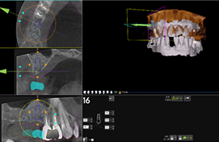

圖三、電腦模擬搭配導航植牙手術 (來源:楊濡瑄醫師)

(左)手術前用電腦模擬植牙位置。(右)手術中利用導航系統精準植牙在計畫位置。